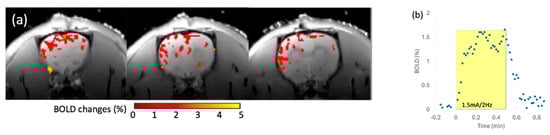

The in vivo rat brain imaging at 9.4 T did not exhibit appreciable signal loss adjacent to the PTFOS electrodes in the anatomical images when using the T1W, T2W, PD, FLASH, and UTE sequences (Figure 8). The signal loss on top of the brain in the FLASH image was due to the high sensitivity of the imaging sequence (FLASH) to the susceptibility mismatch induced by the surgical procedure, but not because of the PTFOS device. We also obtained good diffusion tensor fiber tracks in the PTFOS rat images while the connector was present. Compared to the rat with sham implantation, neither the sham Gelfilm nor the PTFOS grid introduced appreciable artifacts to the images at 9.4 T. To assess the impact of the PTFOS electrodes on imaging quality, we examined the SNR in the T2-weighted images. Figure 9 and Table 4 showed comparable SNRs among the sham and PTFOS implantations, in both the brain and the entire imaging volume. For fMRI, the minimal distortion observed in the EPI images in the PTFOS and sham rats apparently resulted from the tissue trauma introduced by the implantation procedure, not because of the PTFOS device. We were able to obtain reasonable fMRI activity readings in response to forepaw stimulation (2 Hz/1 mA) of the rat with the PTFOS implantation (Figure 10).

Figure 10. The 9.4 T fMRI with electrical forepaw stimulation (1.5 mA/2 Hz) on a rat with PTFOS implanted. (a) The colormap representing the brain area, with statistically significant BOLD responses to the forepaw stimulation. (b) The BOLD time course in response to the electrical forepaw stimulation (yellow block).